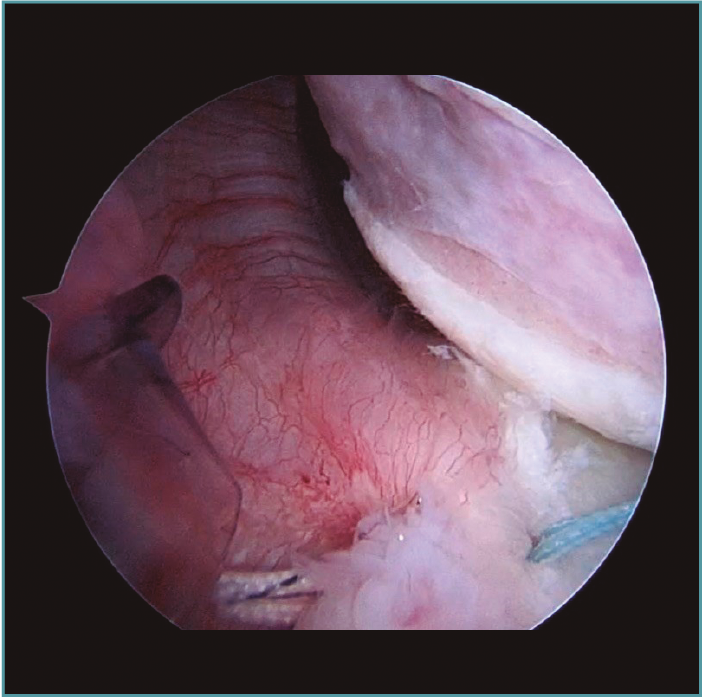

Al realizar la anamnesis, prestamos especial atención a estos síntomas ya que estos episodios repetidos de subluxaciones o microinestabilidad pueden conllevar a lesiones muy complejas e irreparables de la cápsula o, sobre todo, en el cartílago glenoideo (Figura 2).

Figura 2. Visión desde portal posterior del hombro derecho. Se observa una lesión intrasustancia de la cápsula anterior.